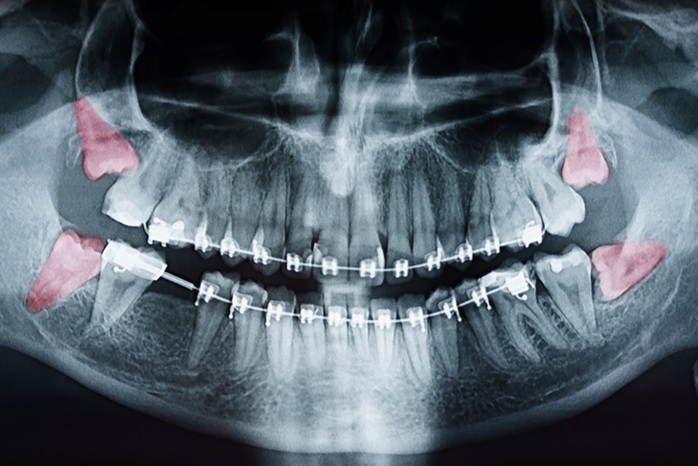

Por justamente serem os últimos dentes a se formarem em nossa arcada, de maneira geral é recomendado extrair os dentes do siso quando não houver espaço suficiente para acomodá-los ou ainda quando estiverem inclusos ou semi-inclusos, permanecendo totalmente ou parcialmente retidos no interior do maxilar (sisos superiores) ou da mandíbula (sisos inferiores).

Após o exame clínico, o ortodontista solicita uma documentação ortodôntica que irá guiar o tratamento. Junto com a documentação será recebida a radiografia panorâmica, que auxiliará o ortodontista a avaliar a necessidade de extração de um ou mais dentes do siso.